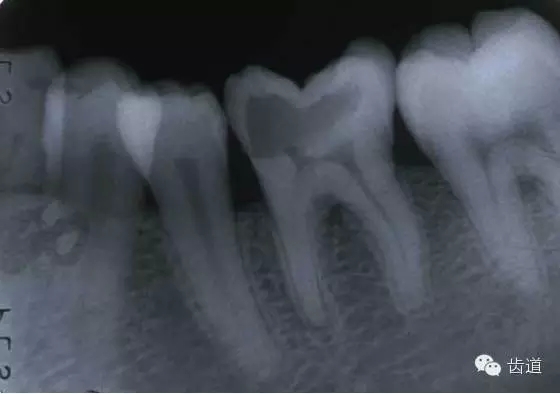

左上7近中頰根器械折斷

右上6腭根器械折斷